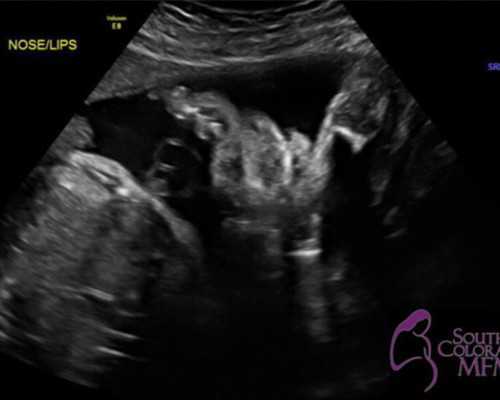

香港检查是经过查验母亲血液判别胎儿性别的办法,抽取孕妈妈手臂静脉血液大概12ML做检查,在母血里分离出胎儿的游离DNA,检查DNA里是不是包括有Y染色体基因,发现有Y染色体基因,即是男宝宝,相反即是女宝宝。上面我们提到母体和女宝宝是不具备Y基因的,除非是在怀有男宝的状况下。香港验血查性别,孕七周就可以做,可靠性高,属于无创性检测,避免流产的危险,准确率高达99.4% 以上。

香港验血 的原理是通过抽取的孕妈咪的血液进行化验,利用基因工程检测技术从母体中检修及分离出胎儿的游离DNA片断后进行判定是否含有男性Y遗传物质DNA片断,从而确认的过程。有Y染色体就是儿子,反之是女儿。

孕妇的血液标本被抽出后,首先经过两次高速离心处理,将上层的清液移入新的无菌管内,冷冻保存备用。然后应用试剂将上清液中的DNA提取出来,将其染色,放在在紫外灯下观察。如果看到SRY的条带意味着是男孩,没有则表明是女孩。胎龄满6周准确率高达99.99%